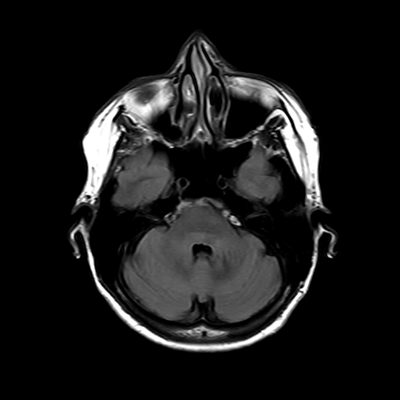

You also obtain an MRI of his brain once it's clinically safe to do so.

MRI brain (FLAIR)